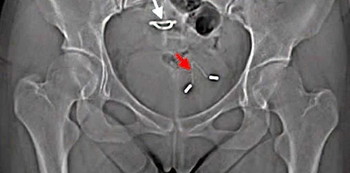

They then performed an X-ray and the findings were shocking!

The X-ray revealed that the IUD had punctured her uterus and moved to her bladder.

What happened to her is an example of uterine perforation that happens to approximately one in every 1000 women who uses an IUD, the Medical report stated. It isn’t common but it can and does happen.